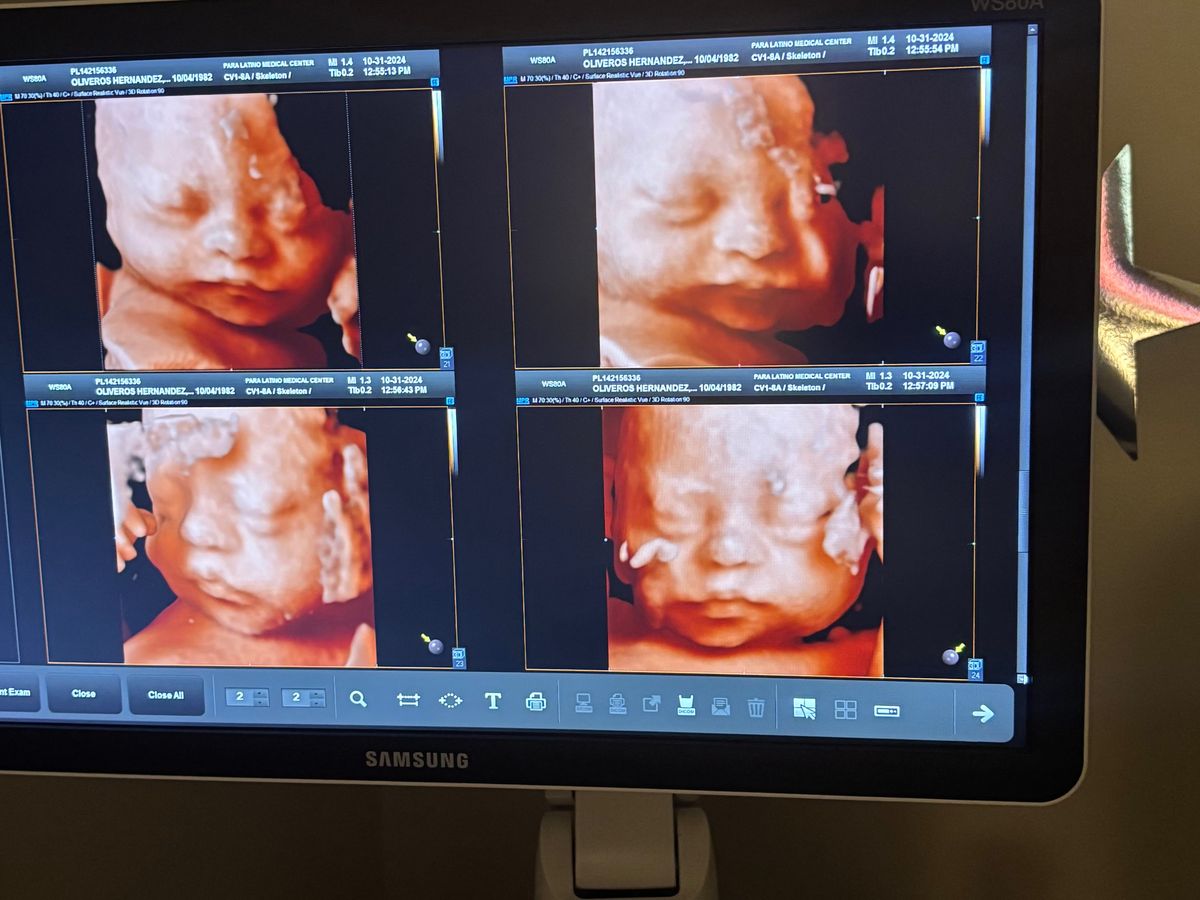

Today, I’m starting this fund in hopes of being able to get some help to pay off what has tragically happened to my mother to start 2025. Unfortunately, she found out on January 1 that the baby boy “Daniel Alejandro “ she was expecting had suddenly passed due to his heart-stopping. Being only a few days from coming into the world, Daniel wasn’t able to experience coming into the world to a fantastic woman of a mother, my mom Rosa. She had to deal with the pain of labor and suffering, but she knows that

We are incredibly heartbroken, but we know God has a place for him in heaven. He was such a smiling baby boy, and it’s painful not being able to help my mother raise another kid. My three younger siblings and I know we will have Daniel's blessings forever.

Hoy, estoy iniciando este fondo con la esperanza de poder obtener algo de ayuda para pagar lo trágico que le pasó a mi madre para comenzar el 2025. Desafortunadamente, ella se enteró el 1 de enero que el bebé “Daniel Alejandro” que estaba esperando. había pasado repentinamente debido a que su corazón se detuvo. A solo unos días de venir al mundo, Daniel no pudo vivir la experiencia de venir al mundo de la mano de una fantástica mujer de madre, mi mamá Rosa. Tuvo que lidiar con el dolor del parto y el sufrimiento, pero sabe que Estamos increíblemente desconsolados, pero sabemos que Dios tiene un lugar para él en el cielo. Era un bebé muy sonriente y es doloroso no poder ayudar a mi madre a criar a otro niño. Mis tres hermanos menores y yo sabemos que tendremos las bendiciones de Daniel para siempre. Recurrimos a nuestra comunidad en busca de apoyo durante este momento difícil. Mi mamá siempre ha sido la que tiende una mano y ahora te pedimos tu amabilidad y generosidad para ayudarla a cambio. Cualquier donación, por pequeña que sea, irá directamente a los gastos del funeral.